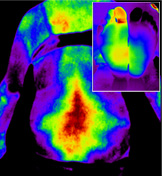

적외선 체열검사 DITI (Digital Infrared Thermal Imaging)

- X-ray, MRI 등으로 확인할 수 없는 신경통, 근육통 등을 확인하기 위하여 적외선을 이용하여 체열 분포의 변화를 확인하는 검사

- 통증이 있는 부위에서는 교감, 부교감 신경의 작용으로 체열이 높거나 낮게 측정되므로 이러한 변화를 측정하여 정확한 통증 부위를 확인 가능

질병에 따른 DITI 분석

허리 디스크